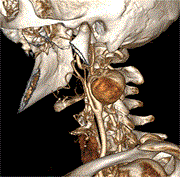

Staged surgery for the treatment of carotid aneurysm

Shiyi Zhao and Dejie Chen

Journal of Surgical Case Reports, Volume 2025, Issue 1, January 2025, rjae849, https://doi.org/10.1093/jscr/rjae849